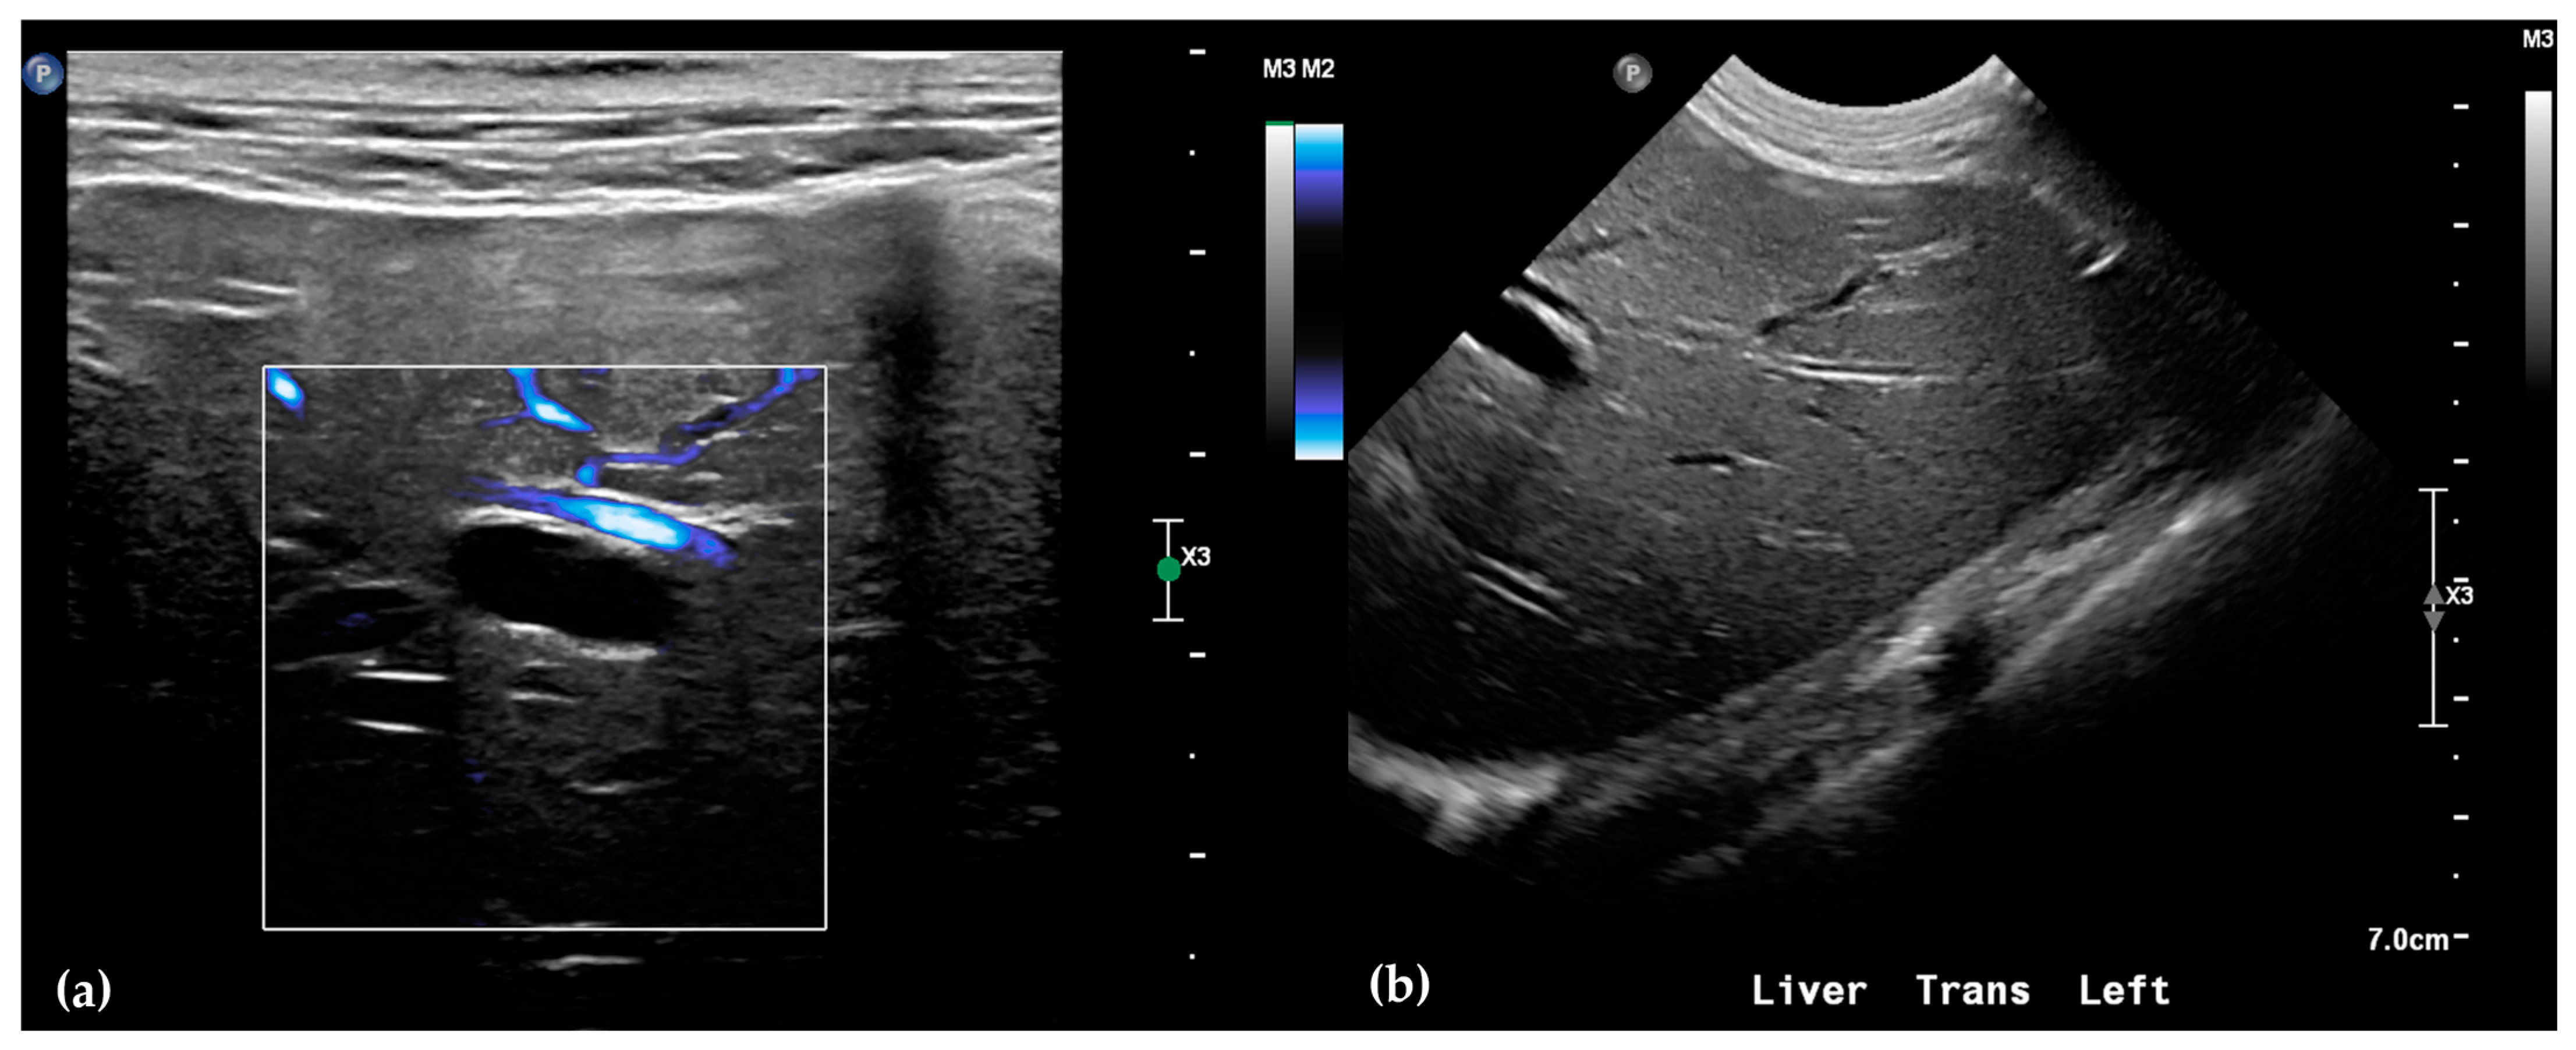

The patient was positioned in sternal recumbency. Helical scans of the abdomen using a multidetector CT were obtained with pre-contrast, post-contrast arterial, portal, and delayed images, all in a soft tissue reconstruction kernel (acquisition parameters: Slice thickness 0.9 mm, pitch 0.8, tube rotation time 0.5 s, 412 mA, 120 kVp, 512 × 512 matrix; Philips Brilliance-40, Philips International B.V., Amsterdam, Netherlands). Prior to contrast administration, the gallbladder was noted to be filled with predominantly mildly hyperattenuating (av. 25 HU) fluid. Dilation of the distal left intrahepatic biliary ducts were again seen (Figure 3a). Following intravenous contrast administration (Optiray 350™ Ioversol, Mallinckrodt Inc., Hazelwood, MO, USA; or Omnipaque 350™ Iohexol, GE Healthcare Inc., Marlborough, MA, USA), multifocal dilation and tortuous narrowing of the CBD was seen and best appreciated in the portal phase. There was increased conspicuity of the walls, both in contrast enhancement and wall thickness (Figure 3b and Figure 4a,b). No intraluminal debris or extraluminal structures to explain the multifocal dilation was appreciated.

Figure 4.

Computed tomographic (CT) post-contrast image (portal phase) at the level of the duodenal papilla (arrowhead) and duodenum (star). Focal dilation of the distal common bile duct (CBD, arrow) (a). Computed tomographic (CT) post-contrast image (portal phase) of the tortuous mid common bile duct (arrow) (b).

Overall, abdominal ultrasound and subsequent CT imaging confirmed multifocal narrowing of the biliary outflow tract. Two regions of marked stenosis were identified: one at the junction of the common bile duct with the cystic duct, and a second at the major duodenal papilla. These findings were consistent with biliary outflow obstruction. There was no evidence of portosystemic shunting or other vascular anomalies.